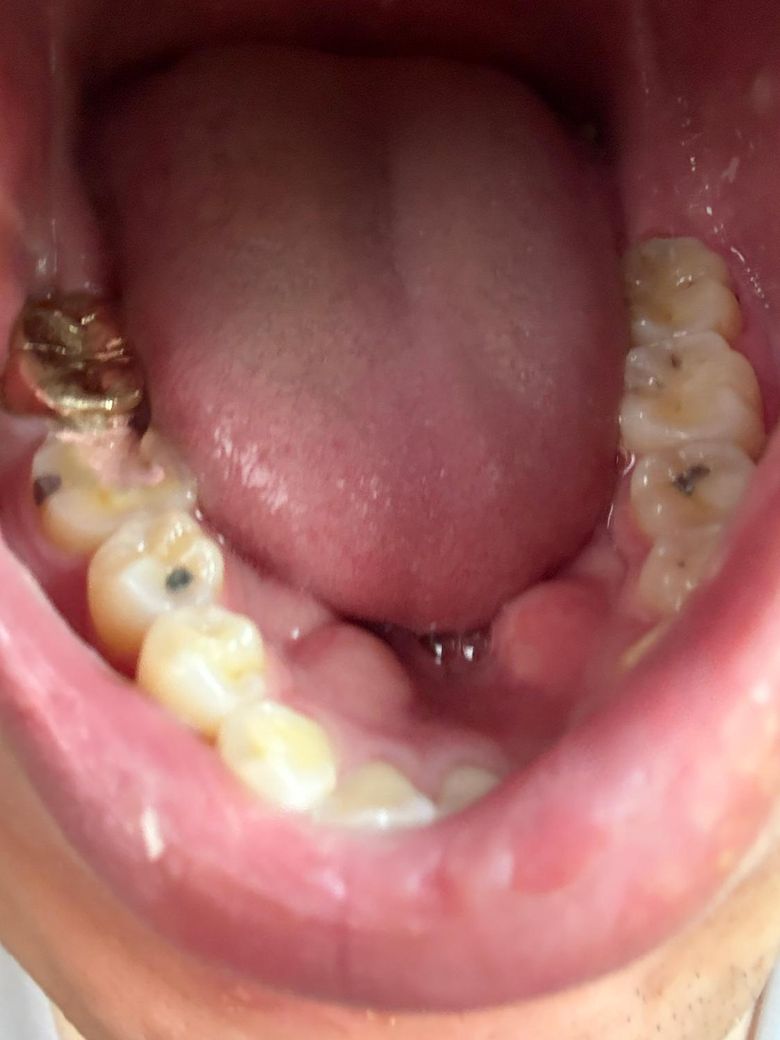

신경치료 질문드립니다! 첫방문입니다 ㅠㅠ

안녕하세요 제가 신경치료를 오늘 받고왔는데요..

오늘이 첫번째 치료였는데

그.. 신경치료 받고나서 위에 뭘 덮어 씌워주셨는데

밥먹다가 그게 신경치료하면서 깎아놓은 곳으로 무너져? 내렸습니다..

제가 신경치료하면서 이런적이 없었는데 이거 정상인가요..?ㅠㅜ

• 1번 째 사진

• 2번 째 사진

신경치료를 하고나서 임시로 메꿔놓은 재료가 살짝 떨어진거 같습니다. 완전히 떨어진건 아니니 너무 걱정하지 않으셔도 될것같습니다.

해당 물질은 치아 내부로 음식물 등이 들어가는 것을 막기 위한 것으로 다 떨어지지 않으면 괜찮습니다.

임시재가 떨어져 나간것으로 보이며, 크게 문제가 되지 않으나 해당부위가 시리거나 통증이 나타날수 있기에 너무 차갑거나 딱딱하고 끈적이는 음식은 섭취하지 말고 가급적 반대 치아로 식사를 하고, 월요일에 바로 치과진료를 권합니다.